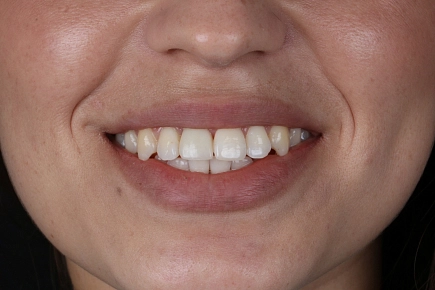

Как подбирается форма будущих виниров?